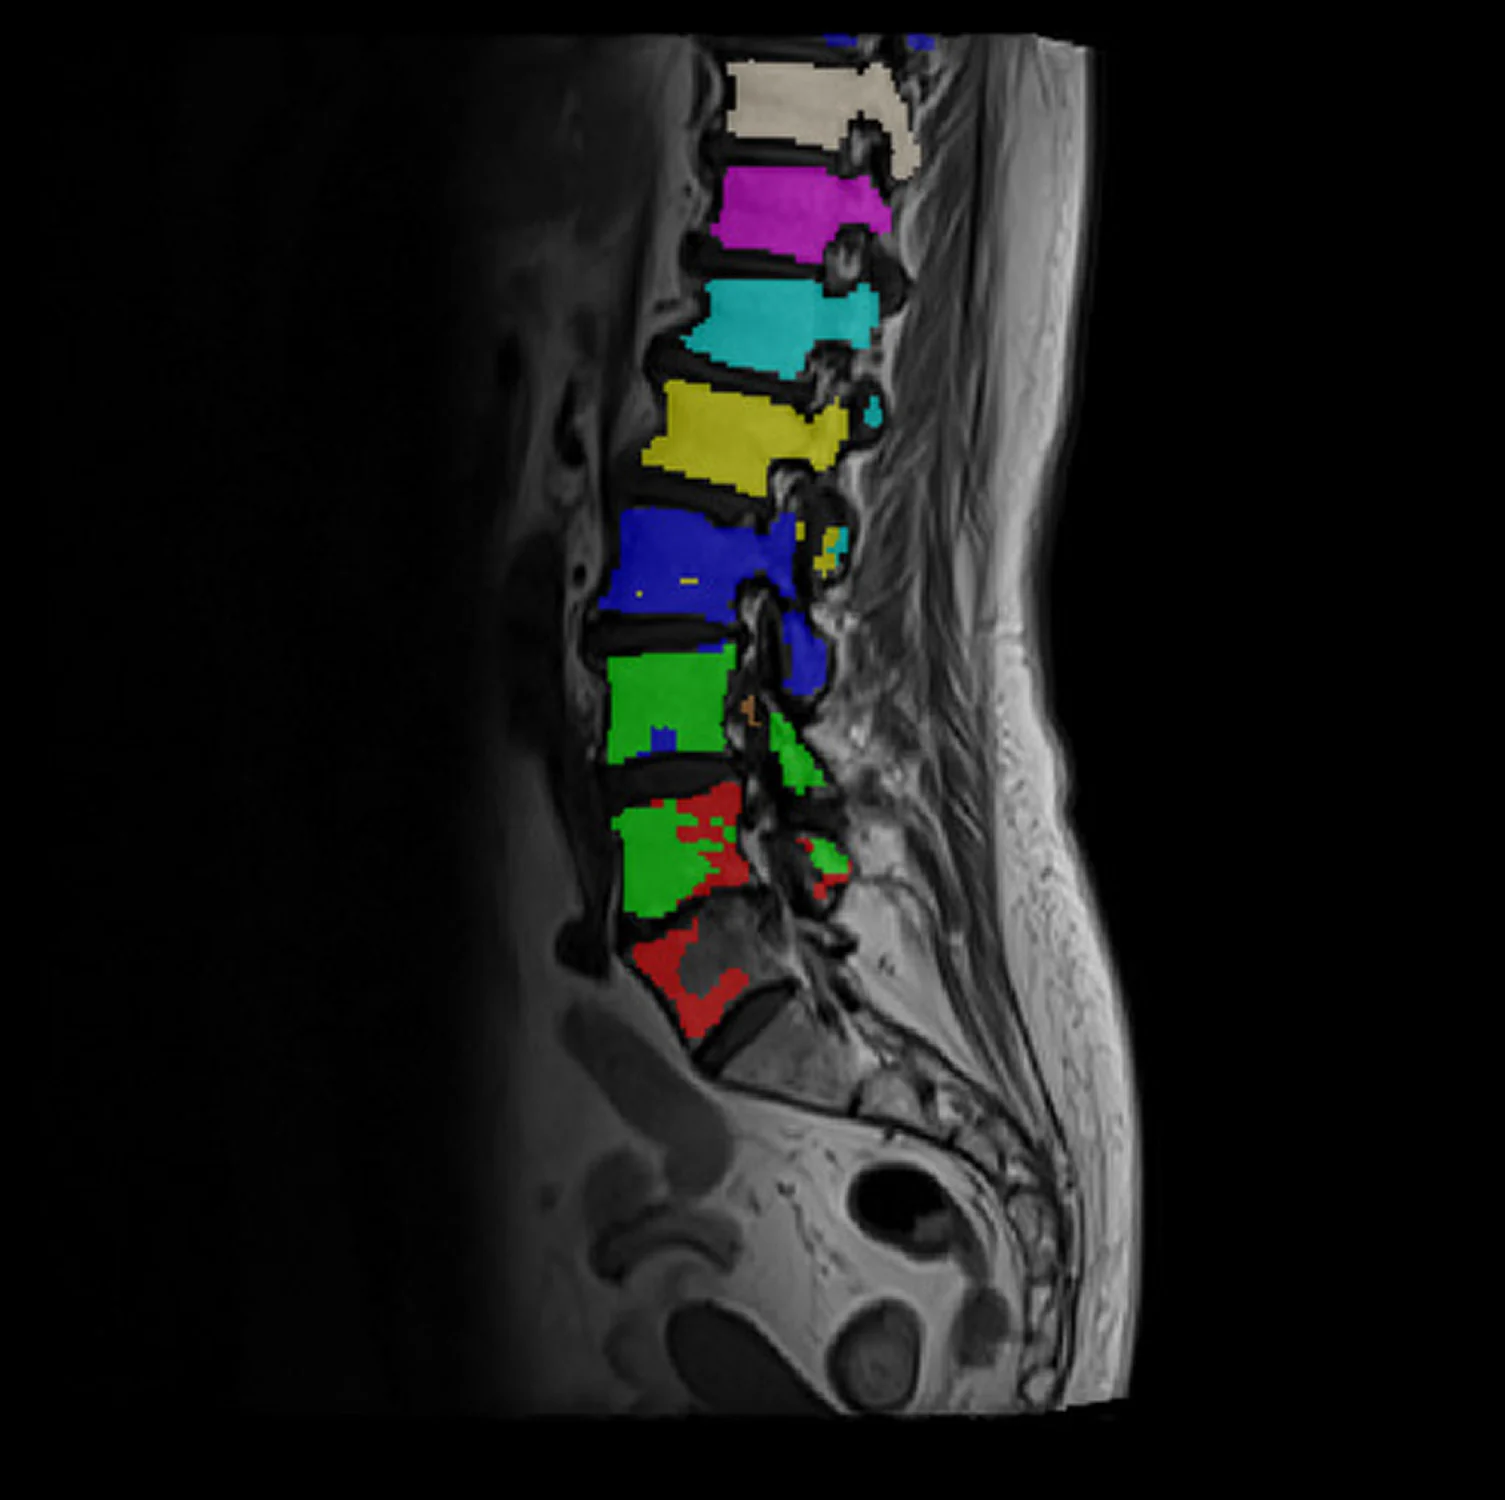

• Accurate Organ Segmentation

Precise segmentation is essential for training medical AI models that require detailed anatomical or pathology-level understanding. High-accuracy masks enable models to measure volumes, isolate target regions, track disease progression, and differentiate tissue types with clinical reliability. Inaccurate segmentation introduces noise into the training dataset, resulting in unstable models, poor generalization, and reduced diagnostic value. High-fidelity segmentation ensures your AI performs consistently, safely, and at a standard suitable for clinical applications.